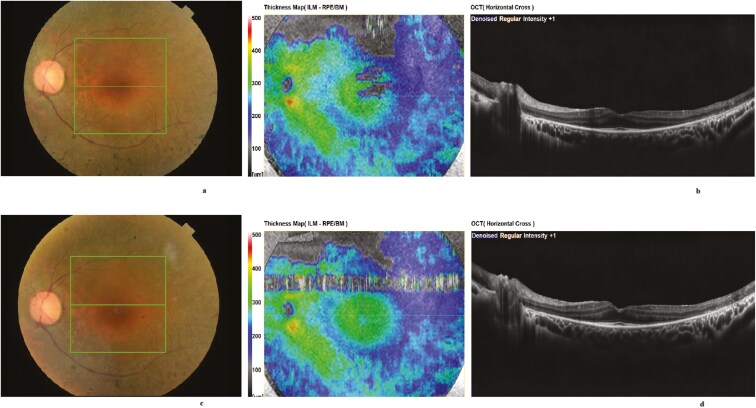

Methods: In this single-center study with a retrospective design, 669 eyes received suprachoroidal implantation of 5 million UC-MSCs. Postoperative assessments were conducted on the first day, third month, and every 6 months thereafter. At each visit, evaluations included best-corrected visual acuity (BCVA), anterior segment and fundus examinations, fundus photography, optical coherence tomography, and visual field (VF) tests. Multifocal electroretinography (mfERG) and full-field stimulus threshold (FST) testing were performed at baseline and every 6 months post-therapy. Procedure-related ocular and systemic complications were methodically documented.